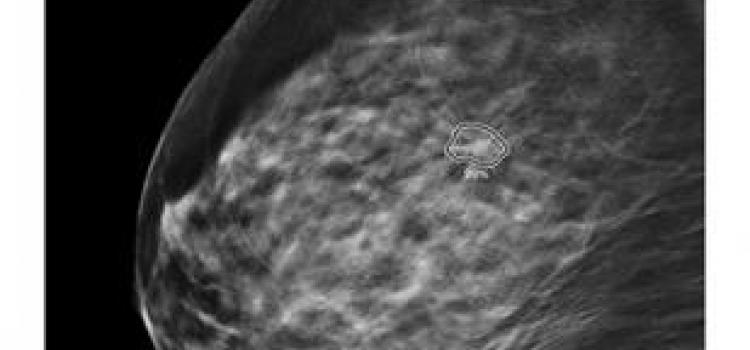

Computer-aided detection software helps doctors make more accurate diagnosis by assisting in the interpretation of medical images.